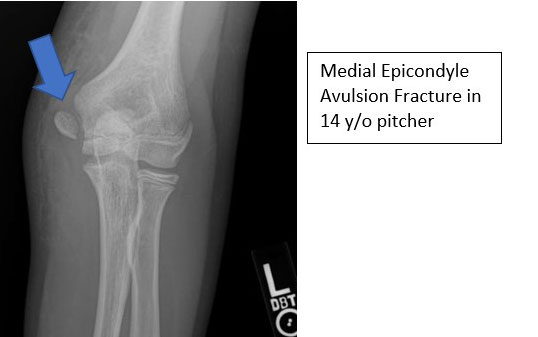

Medial Epicondyle Avulsion Fractures

- True fractures about the medial epicondyle typically occur between the age of 10-14 years

- This is a result of an acute injury typically associated with a discrete event such as a fall or a single throw

- This is not an overuse injury, but instead a result of the older athlete generating enough force to overwhelm the closing physis

- Pre-existing pain or chronic overuse history is NOT usually present

- Swelling is much more pronounced than with apophysitis and may have a loss of motion

- Patient is typically unable to continue to throw and tingling into the pinky and ring fingers may be present

- X-rays demonstrate widening or displacement of the medial epicondyle